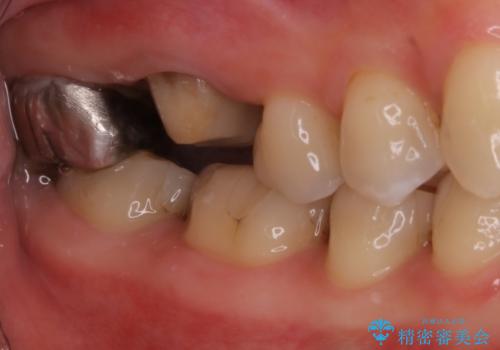

根の病気に対しての治療を行う際、特に再治療の場合においては、無菌的な処置を行うことはもちろん、十分な知識と技術を持つ歯科医師による治療をお勧めしています。

今回の患者様も院長による治療をご希望されたため、福本院長に精密根管治療を行っていただきました。